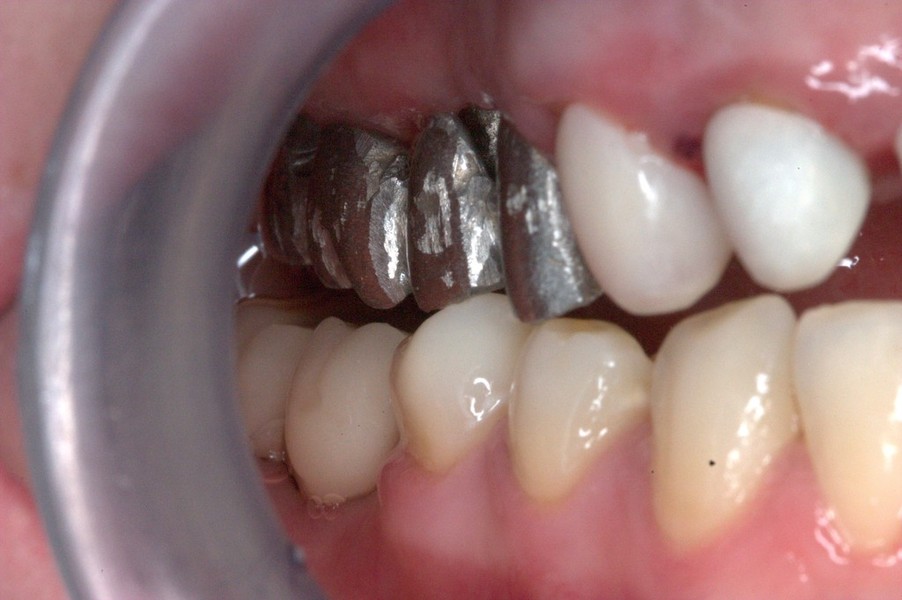

Injerto de mentón para conseguir aumento vertical y solucionar la recesión gingival. Fijación del injerto óseo con tornillo de osteosíntesis.